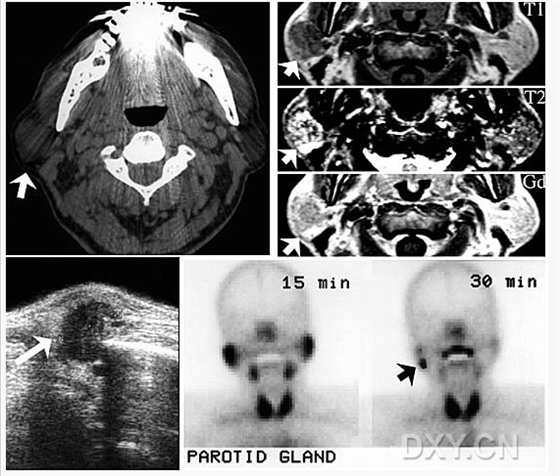

舍格倫綜合征